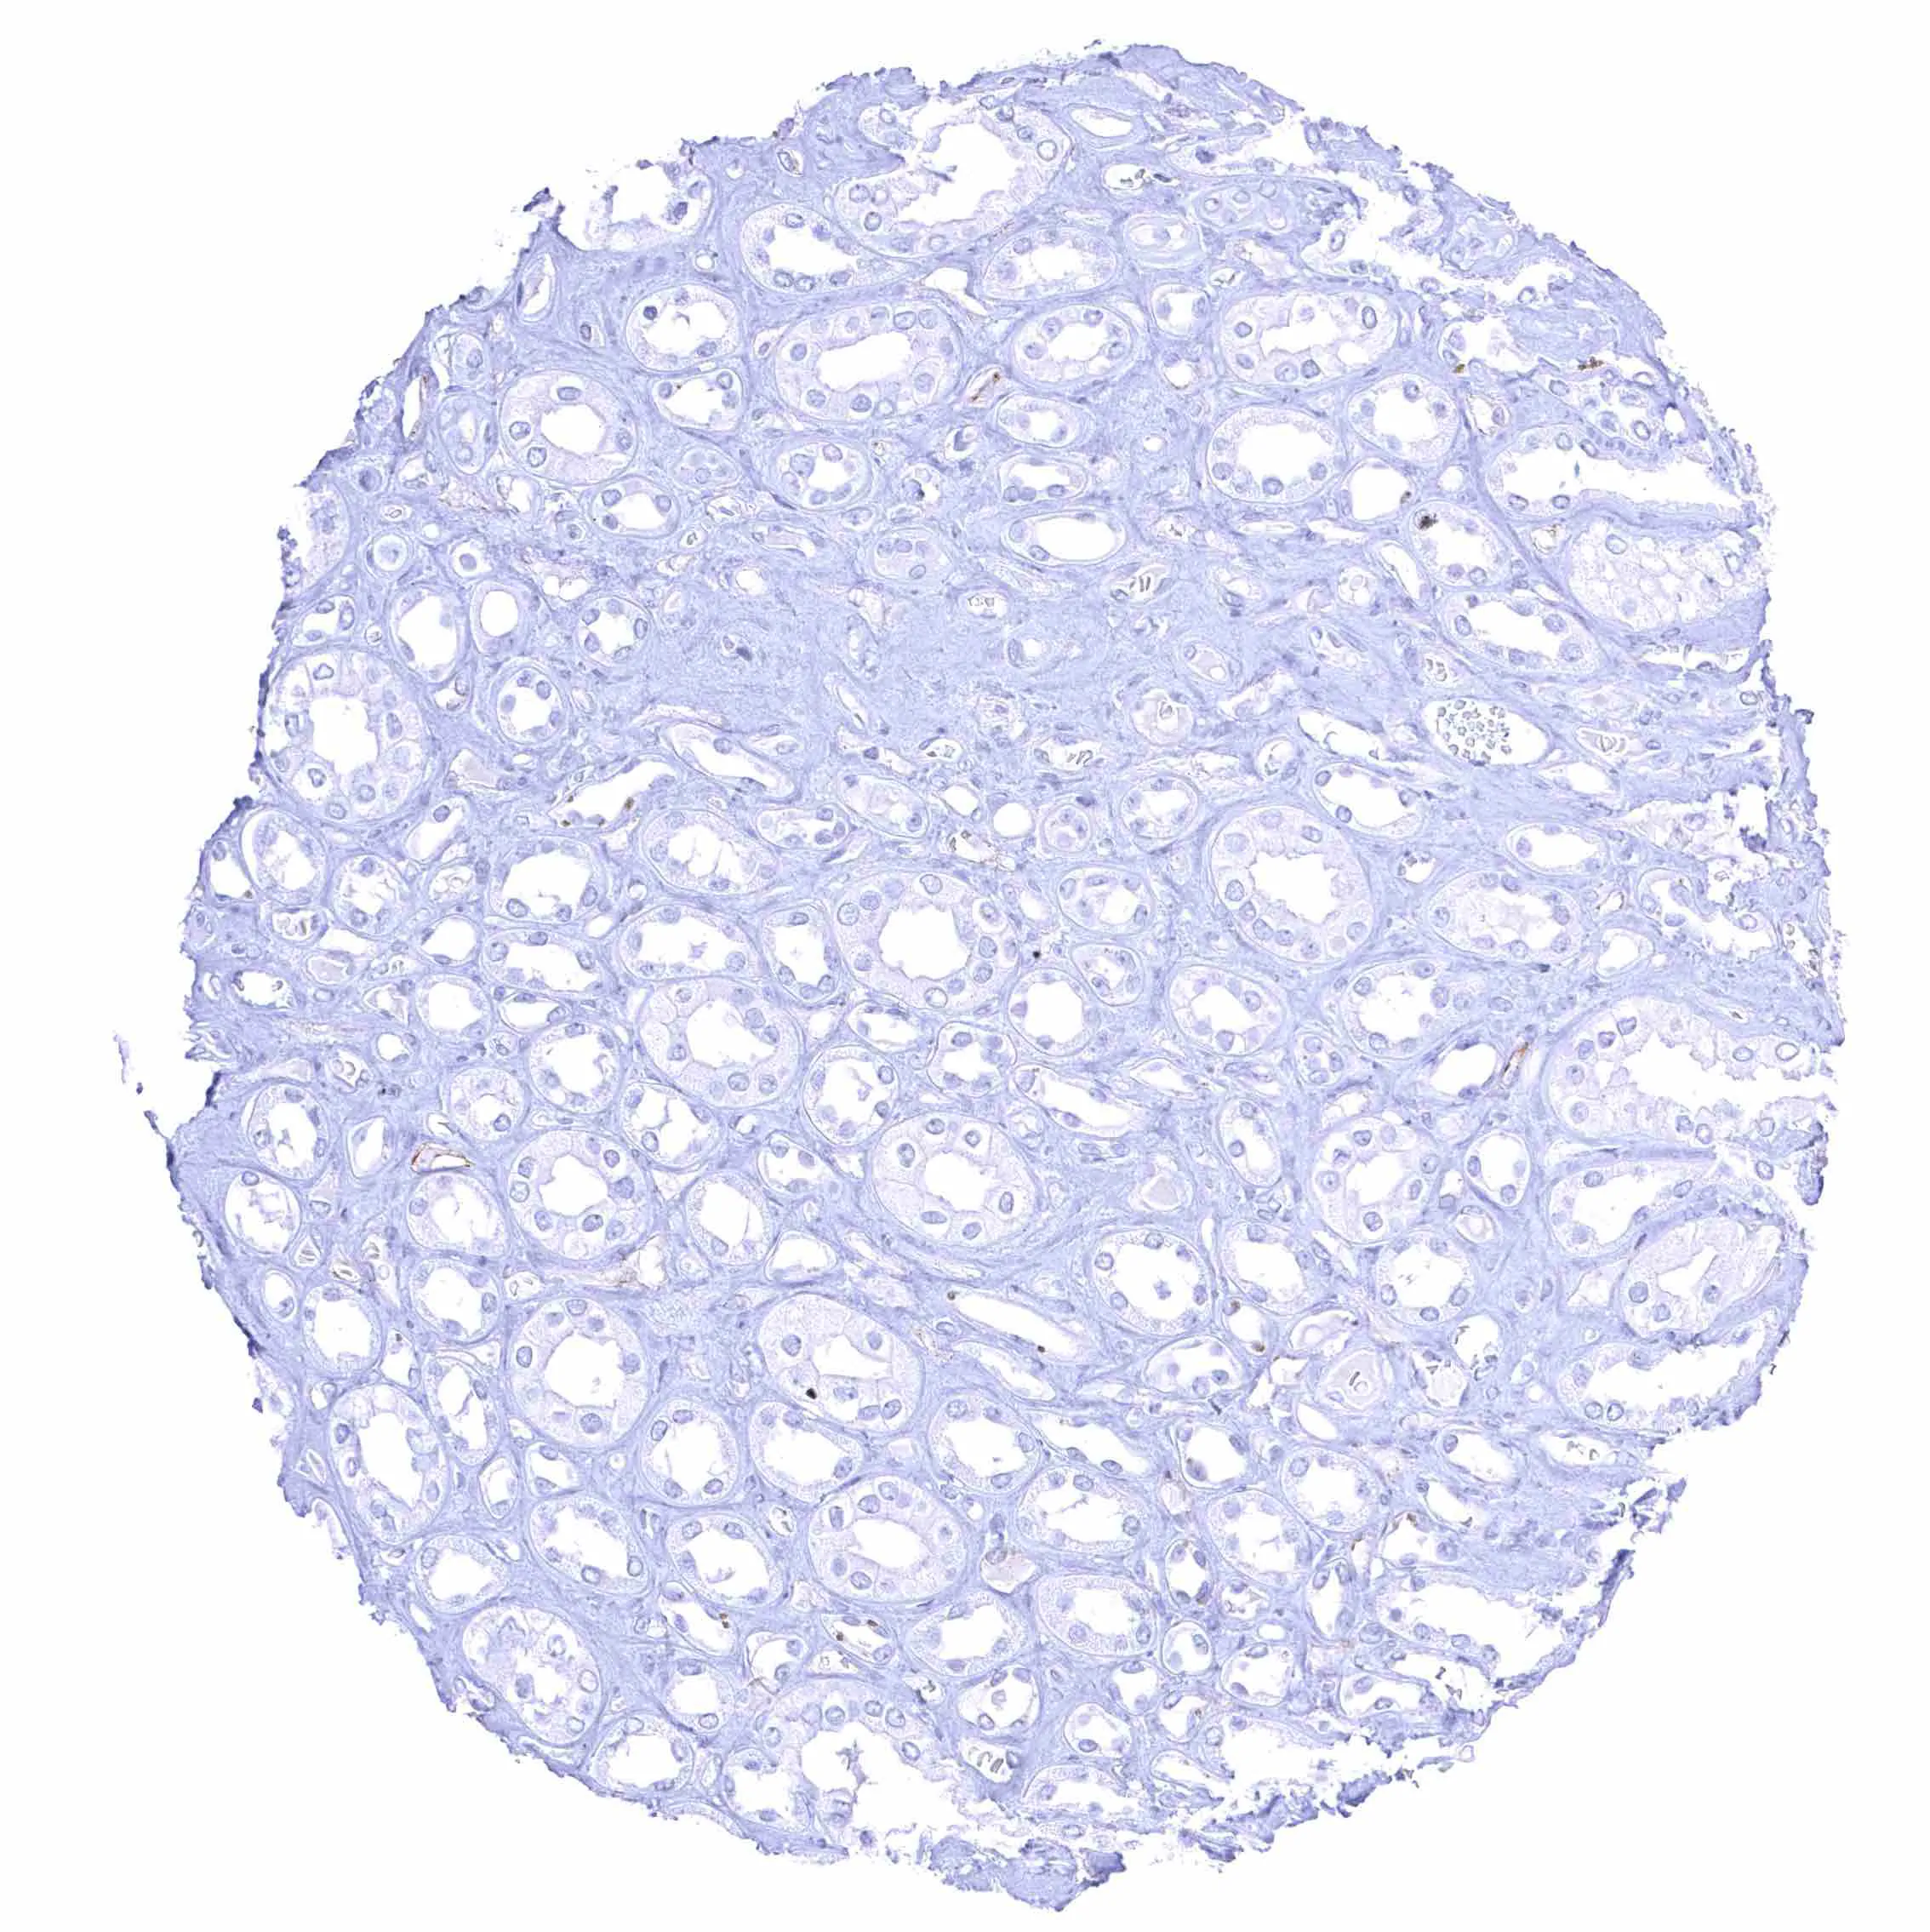

Testis